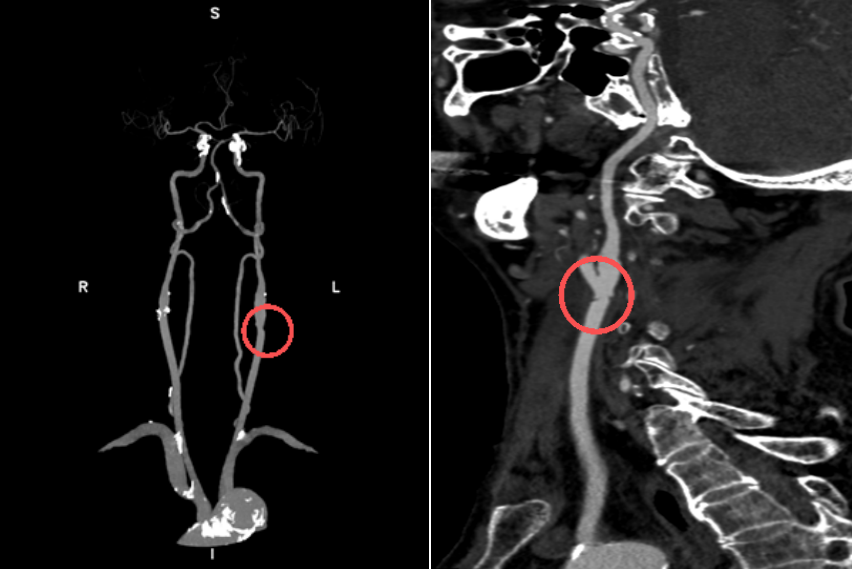

经头颅 CTA、全脑血管造影等检查,发现刘大爷左侧颈动脉窦部出现严重环形钙化斑块,已造成血管重度狭窄,导致同侧大脑供血严重不足,只能依靠对侧颈内动脉通过前交通动脉向左侧大脑中动脉部分代偿供血。

整个过程如同「微雕艺术」。叶信珍副主任医师精准切开颈动脉,将堵塞血管的硬化斑块完整剥离取出,让大脑供血通道重新恢复通血。

术后,刘大爷生命体征平稳,原有的头晕、视物旋转等症状得到显著改善,恢复过程顺利。